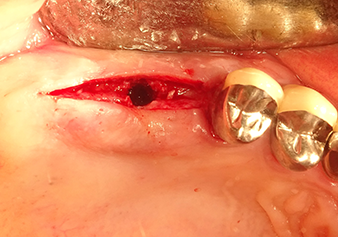

Following atraumatic preparation of the mucoperiosteal flap, the implant position was marked with the I1 instrument and the site prepared – until initial resistance was felt. Piezosurgical instruments were used in an up and down movement without any pressure being exerted. The piezoelectric vibration produced the desired and efficient cavitation.

The I2A instrument (diameter 2.0 mm) was then used to perforate the sinus floor intermittently and on the smallest scale possible. This special piezosurgical method ensures that the Schneiderian membrane is not damaged. When the Z25P was used, the membrane was already lifted slightly by the coolant supplied via the instrument tip (Fig. 3). The coolant quantity was just 50% in order to avoid high pressure in the implant bed.

The Schneiderian membrane is carefully detached with the Z25P instrument (phase 1)

Fig.3: Following marking of the implant position and initial expansion of the bed, the Schneiderian membrane is carefully detached with the Z25P instrument (phase 1).